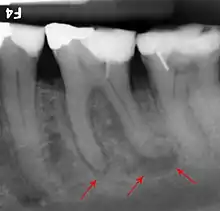

The periodontal ligament becomes inflamed and there may be pain when biting or tapping on the tooth. On an X-ray, bone resorption appears as a radiolucent area around the end of the root, although this does not manifest immediately.[10]: 228 Acute apical periodontitis is characterized by well-localized, spontaneous, persistent, moderate to severe pain.[6]: 125–135 The alveolar process may be tender to palpation over the roots. The tooth may be raised in the socket and feel more prominent than the adjacent teeth.[6]: 125–135

- Radiographs utilized to find dental caries and bone loss laterally or at the apex.